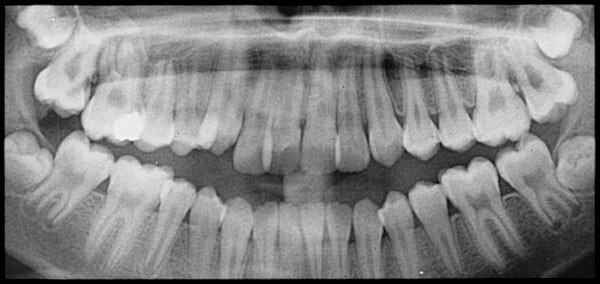

Since no one knows for sure what causes root resorption, it’s hard to know how to prevent it, but since we know there’s a link between orthodontic treatment and root resorption, orthodontists should keep an eye on their patients’ roots. Take regular x-rays and always be on the lookout for decay.

Dentists should also keep an eye on the roots of any patients they know are undergoing orthodontic treatment. Stay alert for any signs of decay and make sure everyone who’s supposed to be helping you take care of your teeth (your orthodontist and your dentist) are all on the lookout for warning signs.